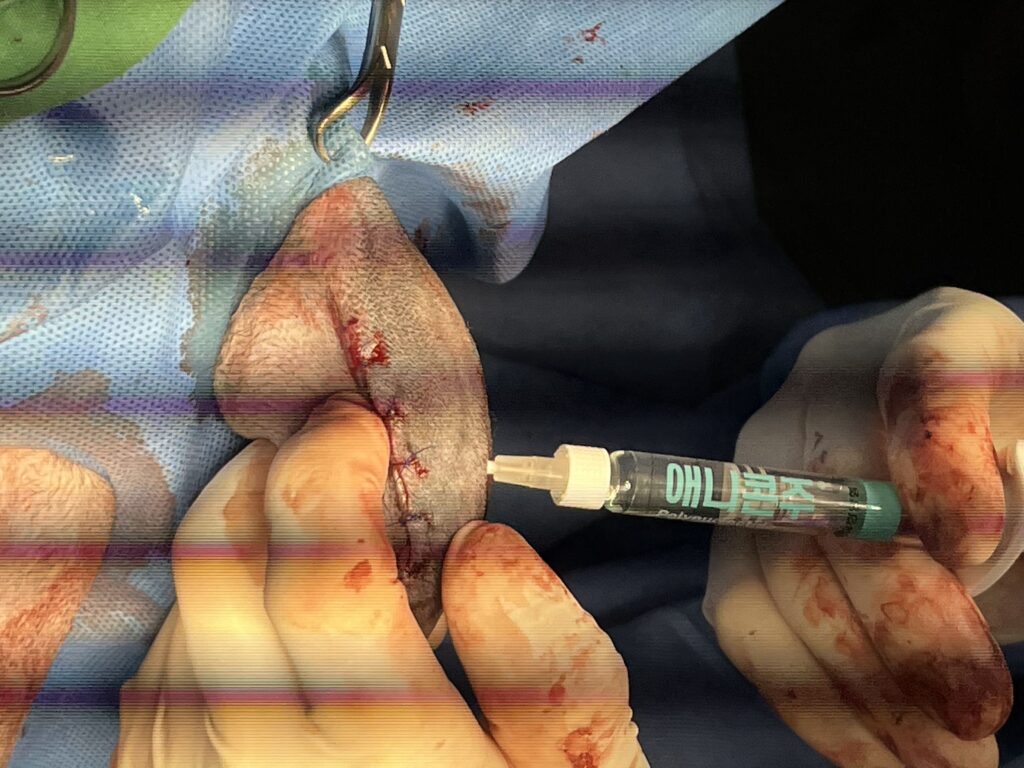

수술사진(좌) / 수술 후 관절주사 주입사진(우) / 출처: 라온동물메디컬센터

라온동물메디컬센터는 수술 후 애니콘 주(Anicon Inj.) 관절 주사를 병행하여 수술 시 통증 완화와 빠른 회복에 힘쓰고 있습니다.